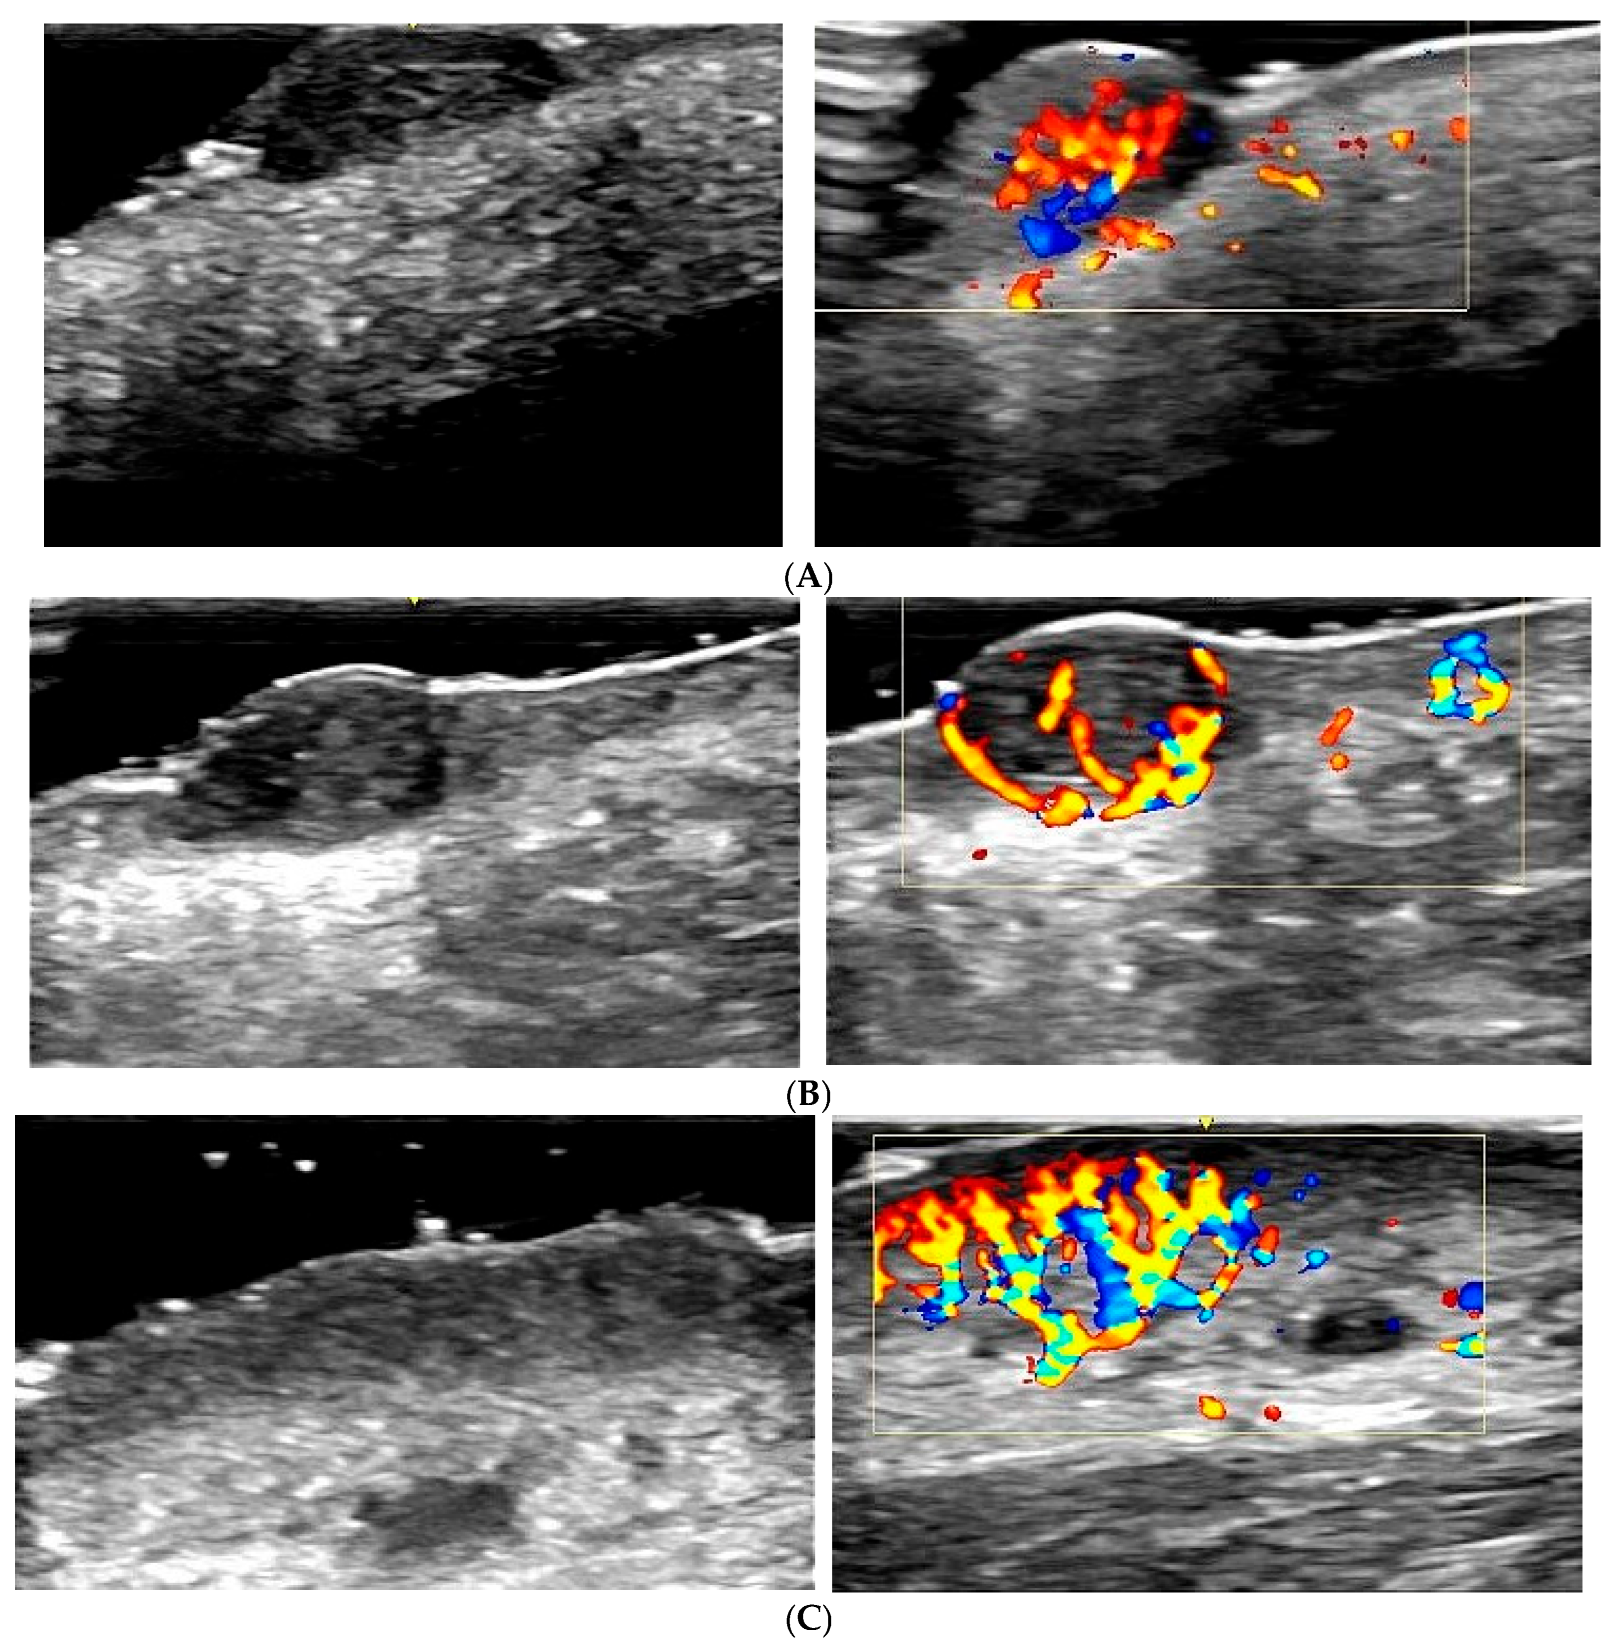

The main vascularization patterns observed in malignant lesions were as follows:

Melanoma: Exhibits an intense and disorganized vascularization pattern, with irregular and chaotic blood flow, indicating neovascularization and aggressiveness (Figure 2A). Colour Doppler is crucial for identifying these features and differentiating melanoma from benign lesions [25,26].

Basal cell carcinoma: Shows pronounced peripheral vascularization, with dilated blood vessels around the lesion (Figure 2B). The peripheral vascularization pattern helps distinguish basal cell carcinoma from other lesions [16,27,28].

Squamous cell carcinoma: Demonstrates intense central and peripheral vascularization, with high-velocity blood flow (Figure 2C). Colour Doppler identifies these patterns as indicative of a malignant and aggressive tumour [18,28,29].

Figure 2. Colour Doppler ultrasound features of malignant cutaneous lesions. (A) Melanoma: Intense and disorganized vascular flow with irregular, chaotic patterns throughout the lesion. These findings are indicative of neovascularization and aggressive biological behaviour. (B) Basal cell carcinoma (BCC): Prominent peripheral vascularization with dilated vessels surrounding the lesion. Although less chaotic than melanoma, the increased vascular density supports malignancy. (C) Squamous cell carcinoma (SCC): High-velocity, intense vascular flow both centrally and peripherally. The combined pattern of disorganized vascularity and signal intensity is strongly suggestive of a malignant tumour.